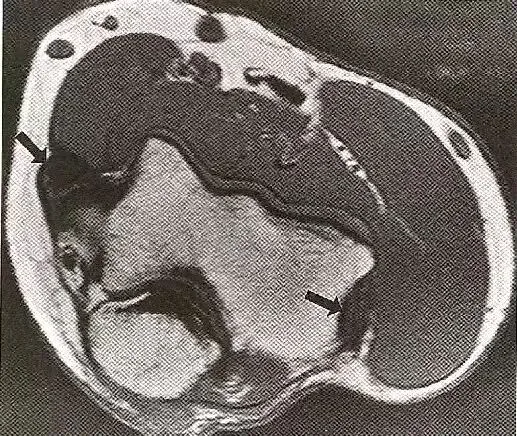

肌腱脱位:  A,肱二头肌长头腱脱位,位于部分撕裂的肩胛下肌腱内。  B,腓骨肌腱(箭号)从腓骨后(大箭头)向外侧脱位,腓骨上支持带已脱离其在腓骨上的附着处(小箭头)。